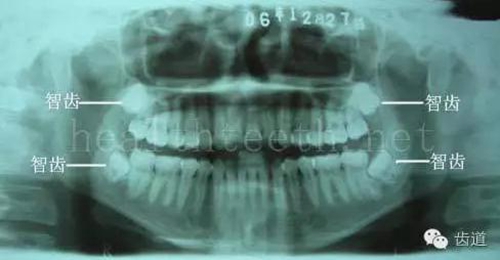

九、關(guān)于智齒(第八顆牙)

四顆長(zhǎng)不出來的智齒

80.jpg